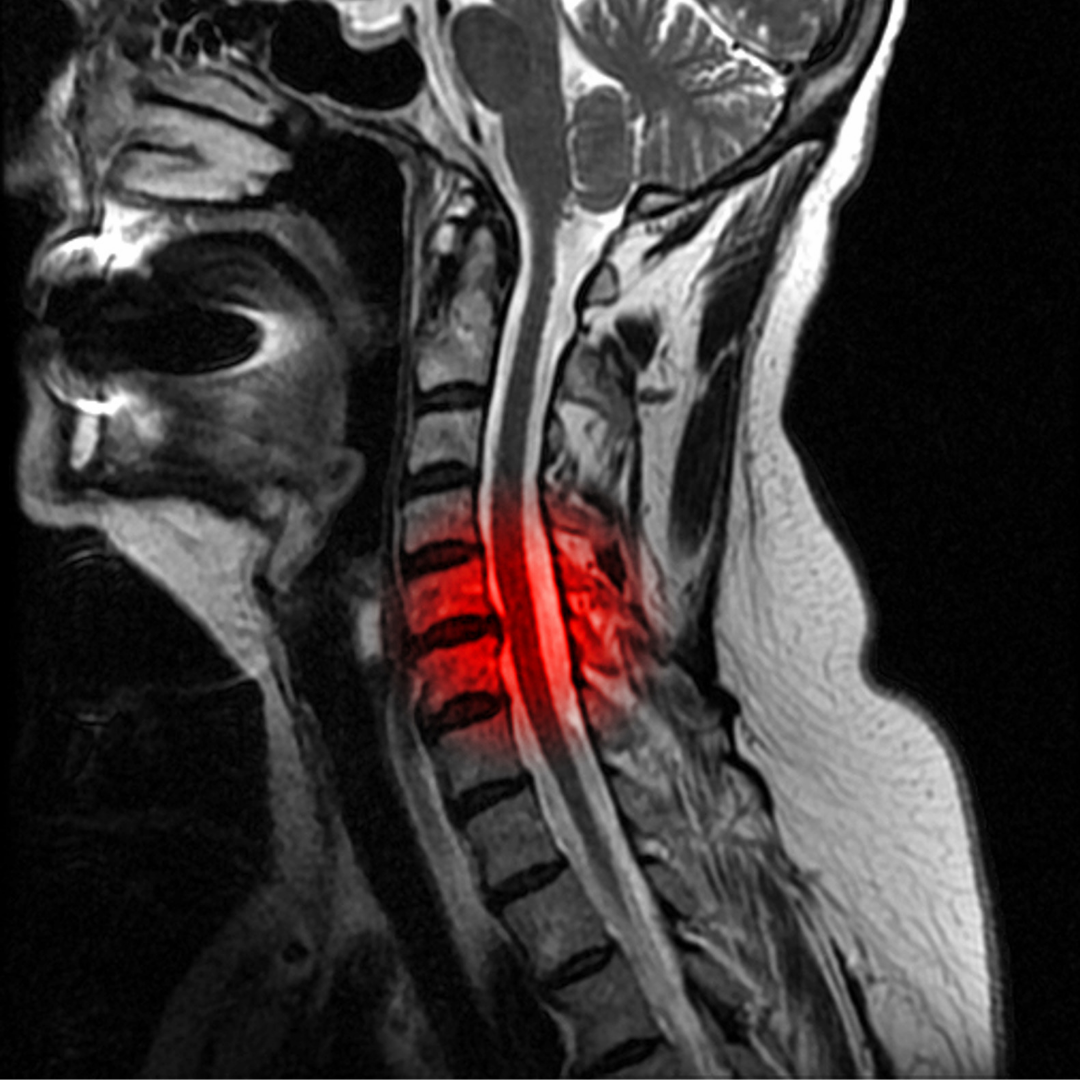

A dor cervical pode variar de leve a intensa e pode ser crônica ou aguda. Ela pode ser causada por uma variedade de fatores, incluindo postura inadequada, lesões esportivas, acidentes automobilísticos e até mesmo o envelhecimento. Independentemente da causa, a busca por alívio muitas vezes leva os pacientes a experimentar diferentes métodos terapêuticos.

A proloterapia, também conhecida como terapia de regeneração tecidual, é um tratamento médico que se concentra na causa subjacente da dor cervical. A abordagem é baseada na ideia de que muitas vezes a dor crônica resulta de ligamentos, tendões, doença do disco intervertebral e articulações enfraquecidos ou lesionados.

Nas sessões de proloterapia, uma solução irritante, como glicose ou outras substâncias seguras, é injetada diretamente nas áreas afetadas do pescoço. Isso desencadeia um processo de cicatrização natural, estimulando o crescimento de tecido conjuntivo mais forte. Como resultado, os ligamentos e tendões enfraquecidos são fortalecidos, aliviando a pressão sobre os nervos e proporcionando alívio da dor.